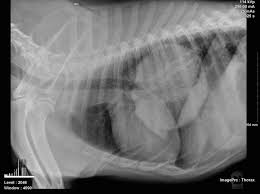

Your dog's chest may enlarge due to the tumor present. If the dog coughs once or twice, it's of no concern, but if. It is estimated that 25% of dogs with a lung tumor show no related signs of cancer. The dog is not coughing up mucus) although the cough may produce small amounts of phlegm or blood. They are rare in both species, but slightly more common in dogs.

Signs of lung cancer in dogs many dogs with a lung tumor show no related symptoms, while other dogs may display one or more of the following symptoms depending on the size and location of the tumor: Carcinomas are malignant tumors that develop from the epithelial tissues in the lungs. The clinical sign characterized as abnormal more common in dogs with lung cancer is a. Your dog's chest may enlarge due to the tumor present. Cancer of the lungs is a progressive disease, meaning it gets worse over time.

Your dog's chest may enlarge due to the tumor present. They are rare in both species, but slightly more common in dogs. Lung cancer in dogs symptoms the symptoms of lung cancer are coughing (which may produce phlegm or blood), exercise intolerance (lethargy), loss of weight or loss of appetite and other respiratory symptoms such as difficulty breathing or shortness of breath. All breeds and both genders appear to be equally affected. The dog may cough up blood, but not mucus. At this stage, the tumor can be removed through surgery. Cancer of the lungs is a progressive disease, meaning it gets worse over time. Most primary lung tumors are diagnosed at an average age of 10 to 12 years in dogs. Symptoms symptoms of lung cancer are coughing (which may also produce phlegm or blood), exercise intolerance (lethargy), weight loss or loss of appetite, and other respiratory signs such as trouble breathing or shortness of breath. #1 lack of appetite as with people, dogs suffer the negative effects of cancer treatments, including loss of appetite. Respiratory problems such as a cough that doesn't respond to treatment is an early indicator that dog lung cancer may be the underlying cause of the condition. Your veterinarian may recommend an fna and cytology or a biopsy, to confirm the diagnosis, and determine exactly what kind of lung cancer is present. Coughing doesn't automatically signal cancer;